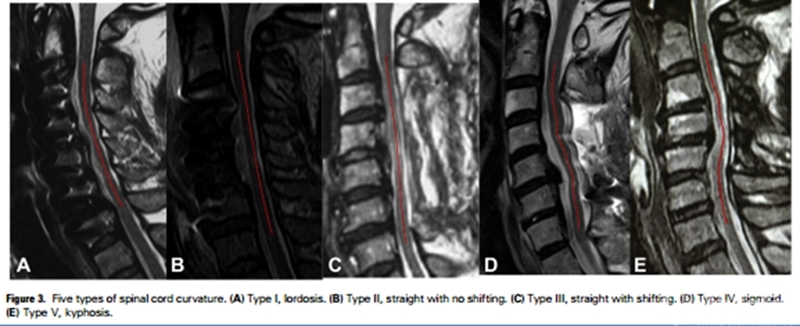

王元博士代表史教授就我国自主创新的手术技术——颈椎后纵韧带骨化椎体可控前移技术(ACAF技术)从“颈椎后纵韧带骨化的MRI脊髓状态评分与JOA评分的相关性”“ ACAF技术如何避免术后骨化物残留”“ACAF技术椎体提拉失败的原因分析及预防”等三个方面进行了诠释(图7)。发言得到了包括日本、韩国、印度等颈椎后纵韧带骨化症高发国家的脊柱外科专家的热情关注与参与,称赞ACAF技术有效解决了长期以来颈椎后纵韧带骨化症手术存在风险高、疗效差的临床难题。会场各国专家就ACAF技术踊跃提问,希望进一步的了解并学习这一来自中国的创新技术,王元博士一一详细解答,取得了良好的与国际接轨、共同学习进步的学术效果。